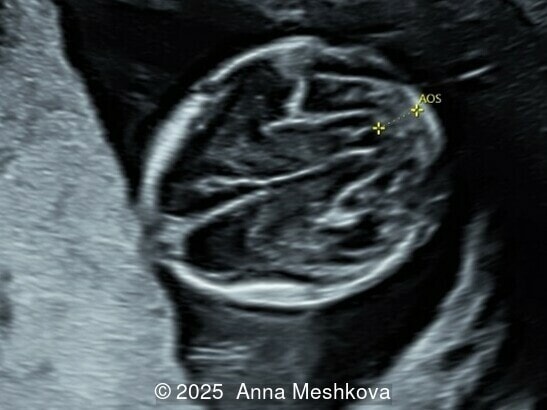

Normal oblique axial view of the brain shows thalami and cerebral peduncles separated by the aqueduct of Sylvius (AOS). A space separates the AOS and occipital bone. The transition between the cerebral peduncles and thalami forms an acute angle.

Image 11 Normal oblique axial view of the brain shows thalami and cerebral peduncles separated by the aqueduct of Sylvius (AOS). A space separates the AOS and occipital bone. The transition between the cerebral peduncles and thalami forms an acute angle.

In spina bifida, the midbrain is posteriorly displaced, eliminating the space between the cerebral peduncles and the occipital bone. The transition between the cerebral peduncles and thalami appears as two parallel lines instead of the normal acute angle

Image 12 In spina bifida, the midbrain is posteriorly displaced, eliminating the space between the cerebral peduncles and the occipital bone. The transition between the cerebral peduncles and thalami appears as two parallel lines instead of the normal acute angle